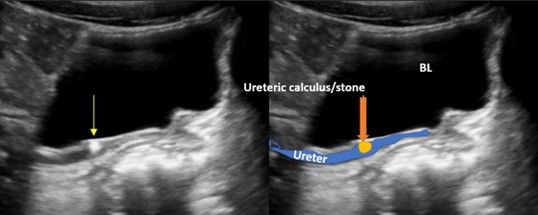

7. kép:

Húgyvezeték kő 2.

Ezen a képen a húgyvezetékben látható szintén egy kő, közvetlenül a húgyhólyag előtt. A sötét struktúra ami a kép felső részén helyezkedik el maga a húgyhúlyag (BL). Alatta látható a tágult húgyvezeték és benne a tágulatot okozó kő, ami világos (echodús) megjelenésű (sárga nyíl).